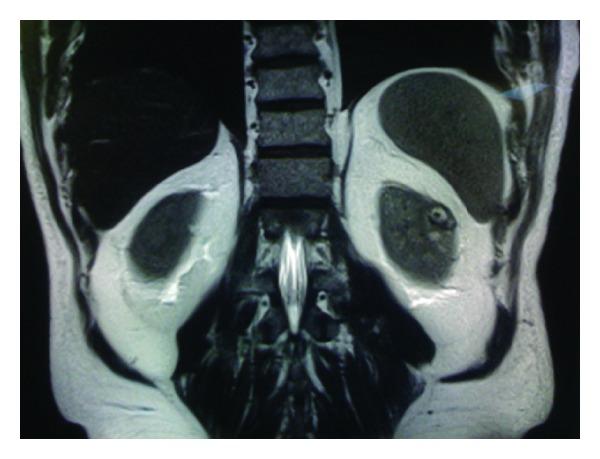

Charts of the initial RANSSs (n = 44), which were performed by a single surgeon, were retrospectively reviewed. R.E.N.A.L. nephrometry system, modified Clavien classification, and M.D.R.D. equation were used to record tumoral complexity, complications, and estimated glomerular filtration rate (eGFR), respectively. Outcomes of the clamped (group 1, n = 14) versus off-clamp (group 2, n = 30) RANSSs were compared.

The difference between the two groups was insignificant regarding mean patient age, mean tumor size, and mean R.E.N.A.L. nephrometry score. Mean operative time, mean estimated blood loss amount, and mean length of hospitalization were similar between groups. A total of 4 patients in each group suffered 11 Clavien grade ≥ 2 complications early postoperatively. Open conversion rates were similar. The difference between the 2 groups in terms of the mean postoperative change in eGFR was insignificant. We did not encounter any local recurrence after a mean follow-up of 18.9 months.